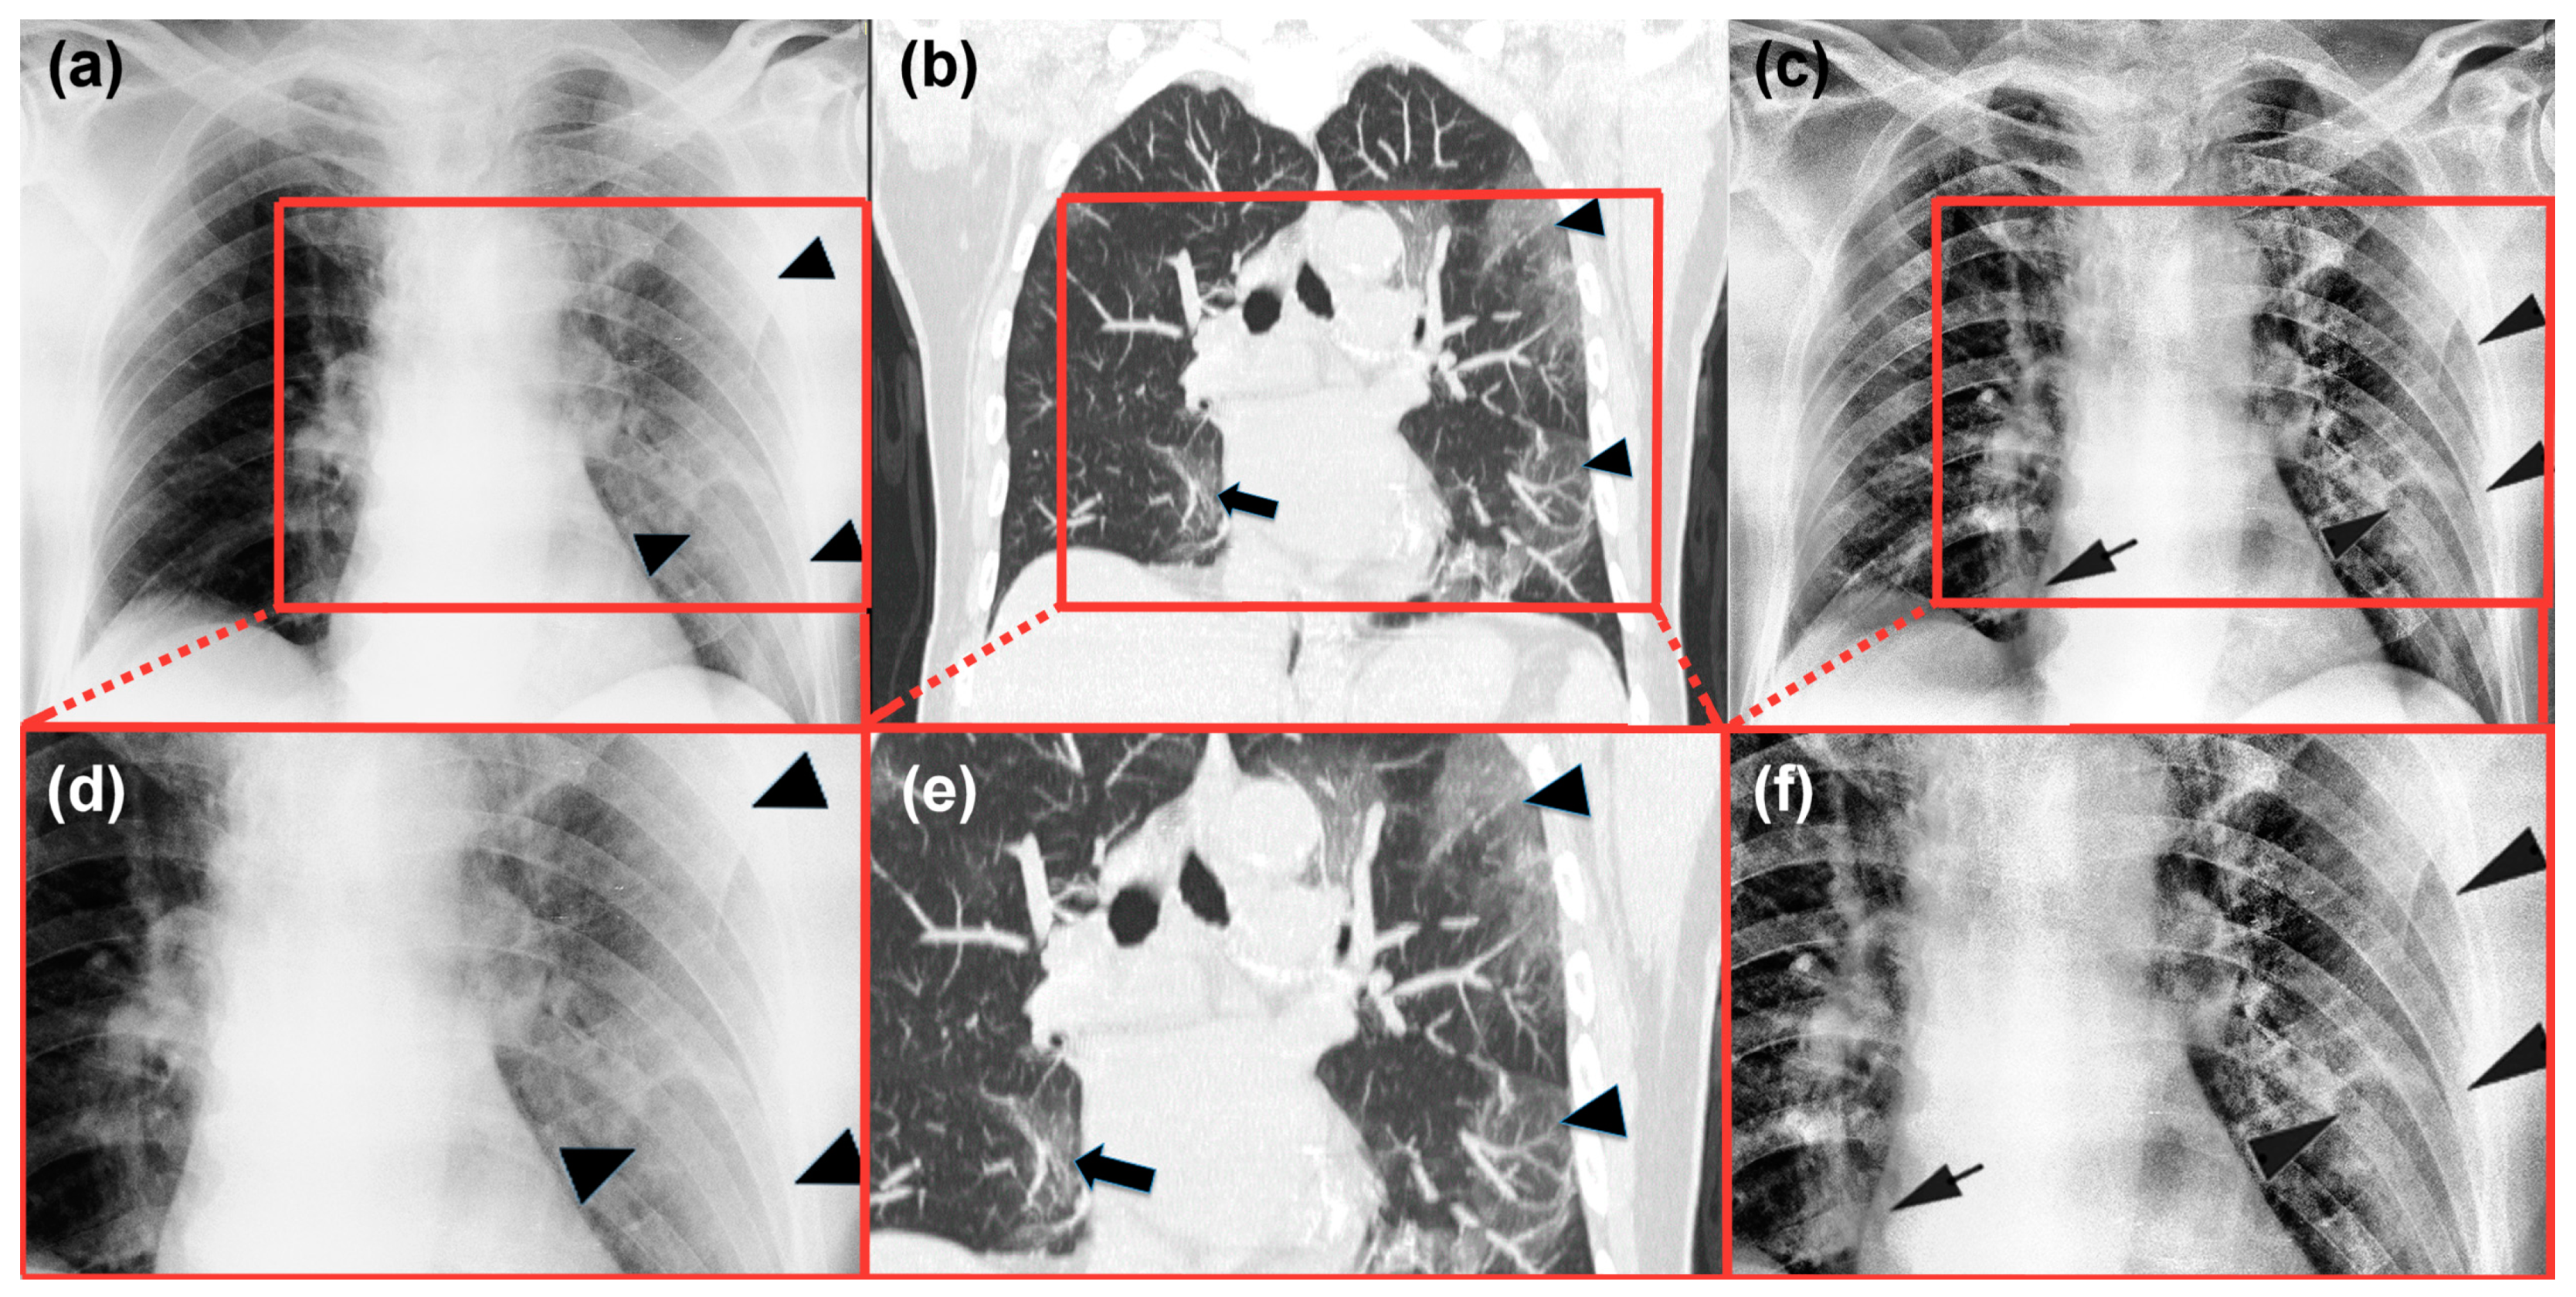

3. Description and Performance Evaluation of the Algorithm

4.2. Radiological Evaluation and Statistics